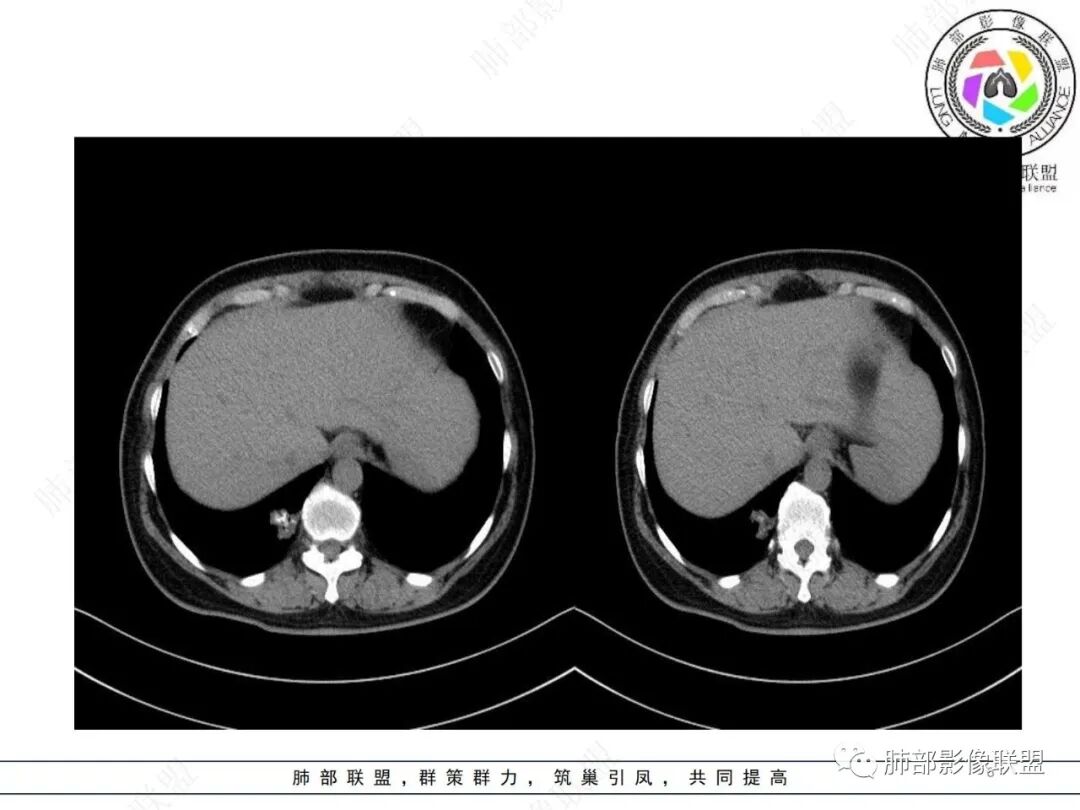

中年女性,右肺下叶后基底段胸膜下不规则稍低密度结节影,内见多发钙化,边缘部分平直,邻近胸膜下脂肪间隙清晰,增强扫描呈均匀轻中度强化,病灶边缘见少许小斑片状影,考虑良性病变,炎性肉芽肿可能,鉴别错构瘤

中年女性 右肺下叶不规则实性病灶中心伴钙化,边缘有分叶、胸膜线样牵拉,增强后中等强化,常规思路考虑良性病灶,但是如果有老片 持续观察这个病灶 是否是在增大,腺癌还是可能的,有的肺癌可伴发钙化就是密度没有这么高,疤痕基础上发生也有可能。

CT强化值应该是大于20HU 轻中度强化

从强化程度来看,强化不支持错构瘤,病灶有膨胀性有收缩及脐样改变,不能排除肺癌(腺癌)

这个形态还是像腺癌,有膨隆有分叶,边缘磨玻璃边界清,非钙化部分轻度强化。腺癌可以钙化的,估计是干扰项

右肺下叶分叶状实性结节伴钙化,胸膜牵拉似有侵犯,增强后轻度强化,倾向恶性,腺癌可能。

典型腺癌(原发>转移)

分叶,边界清楚,中心钙化,实性区中度强化(分叶太明显不支持错构瘤,错构瘤的分叶都是浅分叶,而且错构瘤位于边缘时出现广泛钙化的几率很小,而强化程度不明显,不是肉芽肿强化特点,所以考虑原有疤痕基础上的腺癌或带钙化的转移性腺癌)

原发性结节期粘液腺癌,钙化应该和粘液有关

病理“粘液腺癌”的报告可以“接受”,尽管本例影像学推断有一定难度。